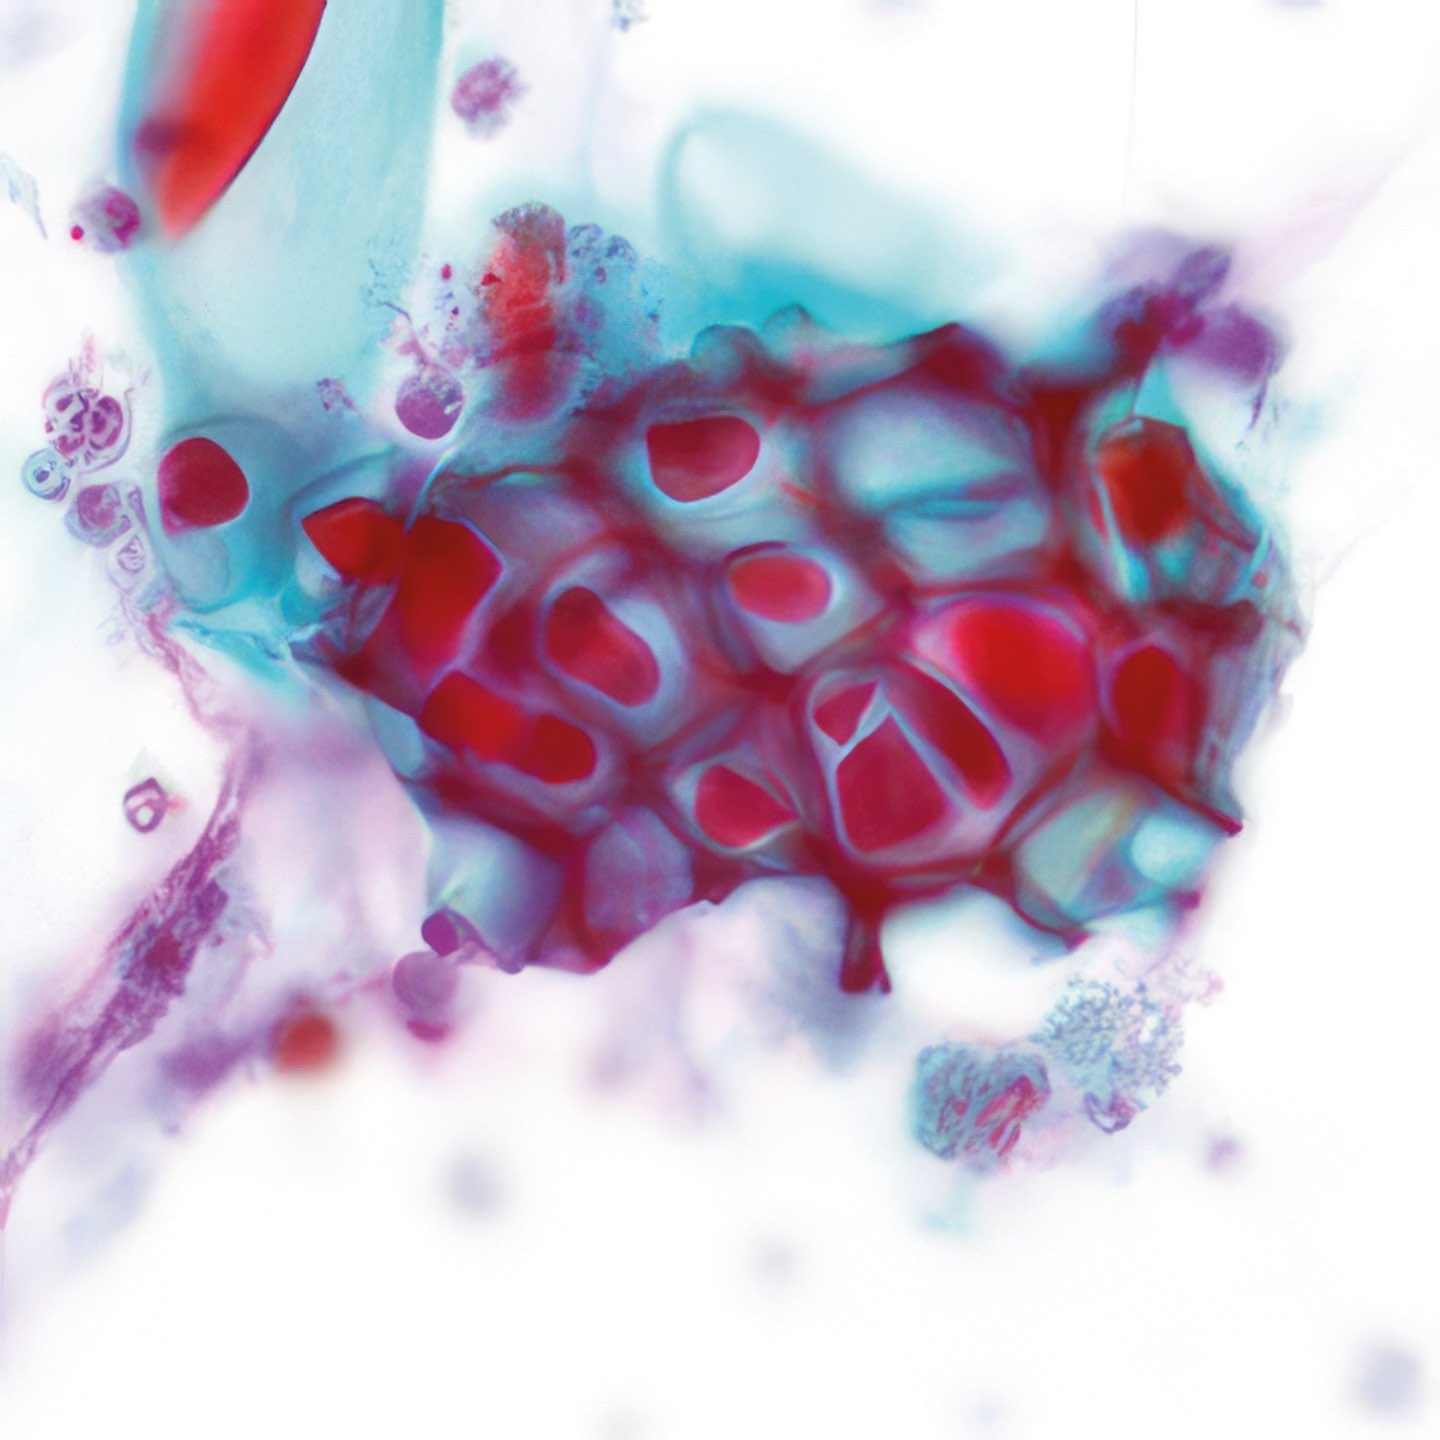

Abbildungen 2 - 4: Pap-Färbung, Obj. 40x.

Die zytologischen Abb. 2-4 zeigen dieselben Zellen. Das Zytoplasma ist breit fragil und enthält massenhaft feine eosinophile Granula. Die relativ grob strukturierten Kerne variieren in Größe, sind aber einheitlich rund, zeigen keine Kerben und enthalten einen gut erkennbaren Nukleolus.

Die eosinophilen Granula im Zytoplasma der Zellen entsprechen einer

dichten Ansammlung von Mitochondrien und gleichen damit den das Hormon

Calcitonin produzierenden para-follikulären Zellen der Schilddrüse. Diese

onkozytischen Tumoren wurden früher als Hürthle-Zell-Tumoren

bezeichnet.